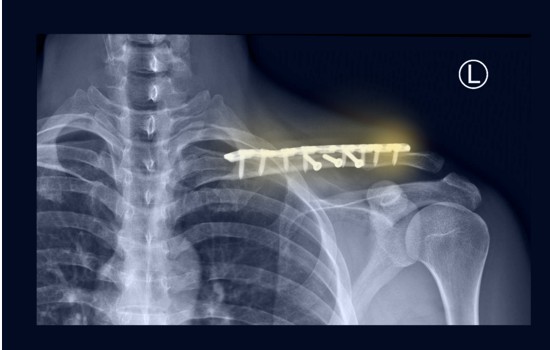

L’intervento di protesi di spalla si svolge in anestesia combinata (generale e loco regionale) mantenendo il paziente in posizione semiseduta. Si esegue un’incisione di 10-15 cm di lunghezza che può essere fatta o sul versante laterale o su quello anteriore della spalla. Si raggiunge il piano articolare e si lussa anteriormente l’articolazione per esporre la testa dell’omero. Se presenti, si rimuovono le neoformate sporgenze ossee denominate “osteofiti” così da preparare le superfici articolari all’impianto della protesi. Queste possono essere applicate con un ancoraggio a press fit quando la protesi s’incastra nell’osso oppure fissate con il cemento nei casi in cui l’osso risulta debole perché osteoporotico.

Gli ancoraggi a press fit riguardano le protesi con steli corti o protesi senza stelo da utilizzare nei pazienti più giovani in quanto il tessuto osseo è più resistente e normotrofico.